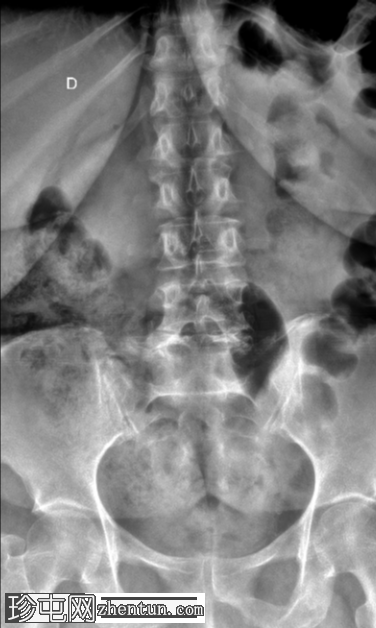

正面

2.png

L5-S1 椎体II度滑脱。

双侧椎间盘缺损。

L5-S1椎间盘间隙缺失,伴有退行性病变。